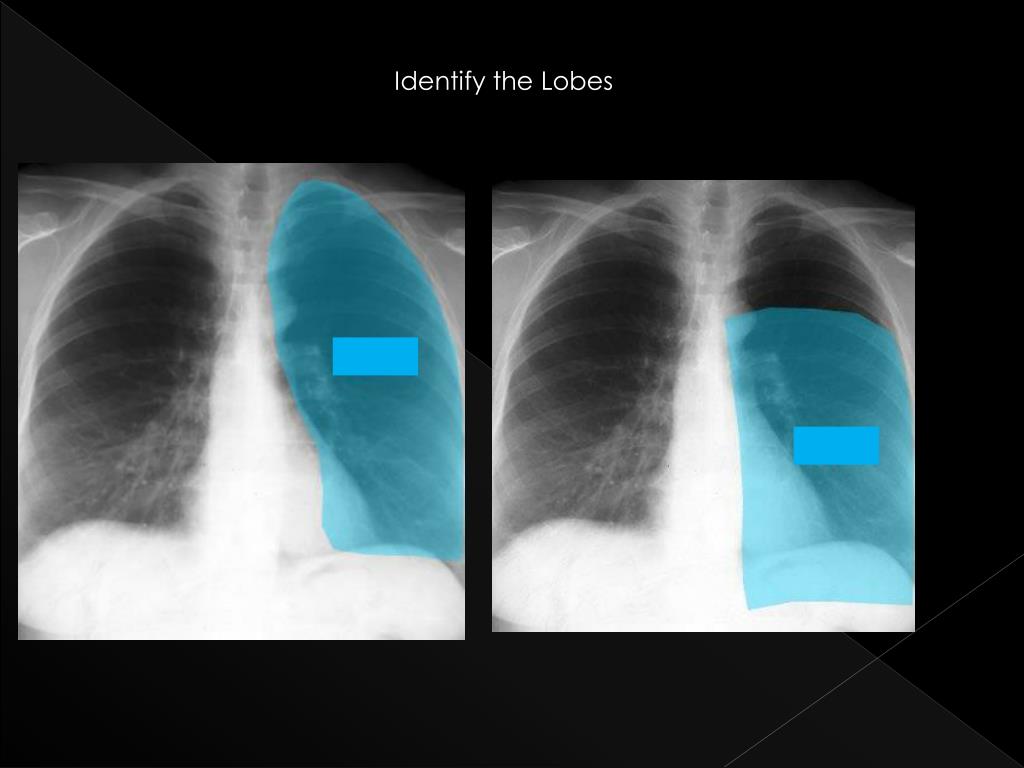

24. Identify the Lobes LUL LLL

26. Identify the Lobes RUL RML RLL